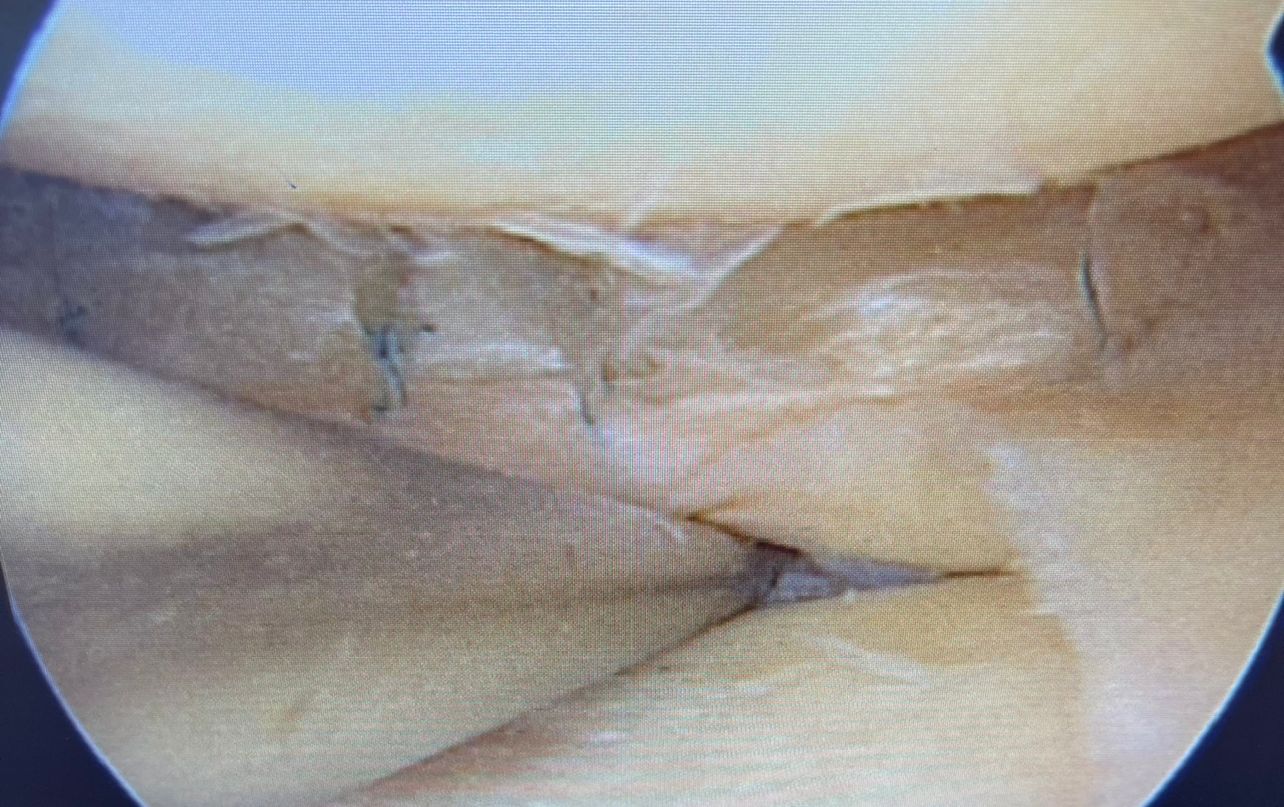

A meniscus repair surgery is a surgical procedure that helps maintain the cartilage in your knee joint. In this process, the surgeon uses a variety of fixation techniques to help retain as much meniscus as possible. This is important to help preserve the knee joint by maintaining as much of the shock absorber cartilage in the joint as possible.

“It’s always important to try to save the meniscus whenever possible. In this case there was a complex tear (with multi-layer splits) of the lateral meniscus. This was repaired using multiple vertical sutures to obtain compression and good hold to restore the shock absorber “